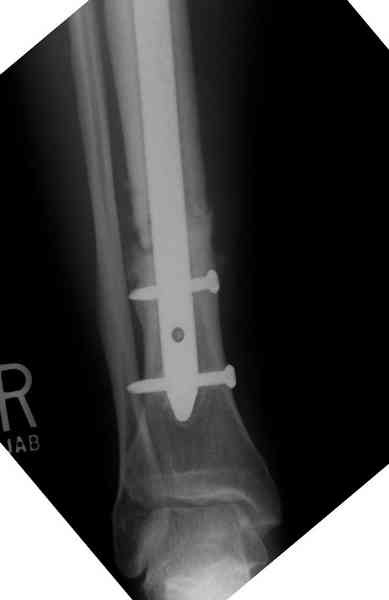

Оперирован в военном госпитале с заменой сегмента

аллокостью большеберцовой кости и после демобилизации явился для постоянного наблюдения по месту жительства.

Наши имели проблему со сращением, пришлось им сделать динамизацию, дополнительную аутопластику.

Снимки представлены.